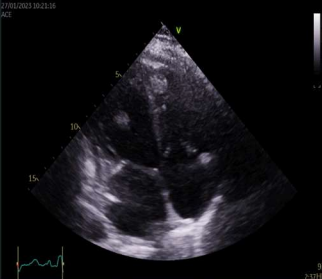

Cardiac magnetic resonance revealed left ventricle with characteristics of post-toxic cardiomyopathy and severely reduced global contractility with EF 34% (Image. 3- midmyocardial late gadolinium enhancement-LGE). Two chamber cine best visualized a cardiac mobile mass (11x7mm) attached to a small stalk to mid segment of the anterior wall of the left ventricle. The mass showed isointense signal on T1 (Image. 4), high intensity signal on T2 (Image. 5) and homogeneous late gadolinium enhancement (Image. 6). Characteristics were consistent with papillary fibroelastoma with differential diagnosis for myxoma or metastasis.

Image 3. CMR- midmyocardial LGE in IVS